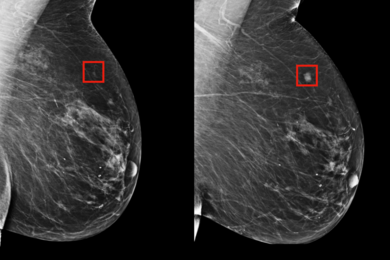

HealthDay News reporter Amy Norton writes that MIT researchers have developed an AI system that can help predict a woman’s risk of developing breast cancer and provide more personalized care. “If you know a woman is at high risk, maybe she can be screened more frequently, or be screened using MRI,” explains graduate student Adam Yala.